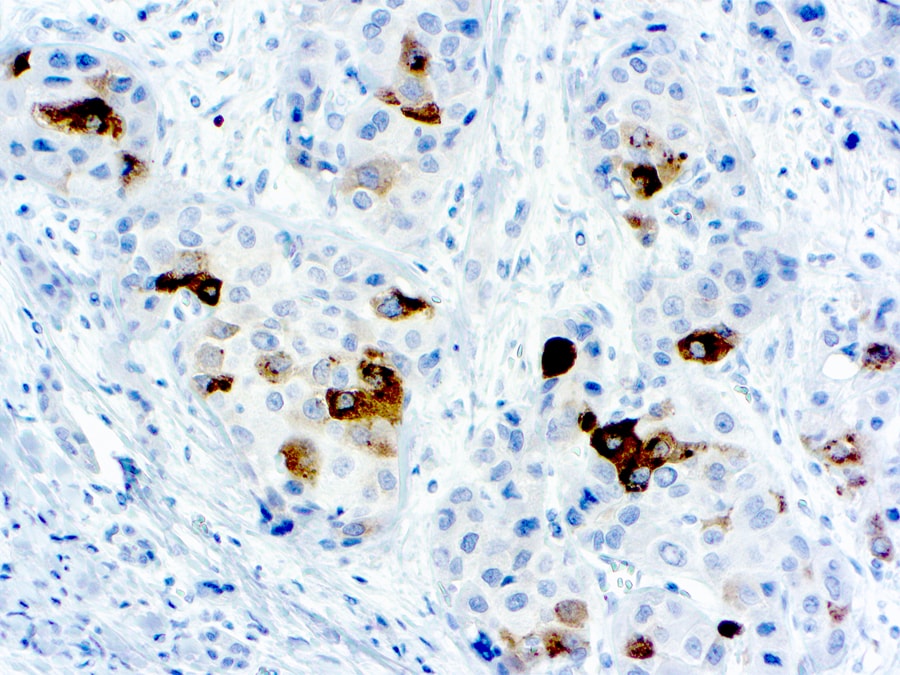

Alpha-1-Fetoprotein (AFP)

This antibody reacts with a-1-fetoprotein. A positive staining in the hepatocytes of fetal tissue was observed. This antibody does not react with any other cell or tissue types.

Clone Polyclonal Rabbit

Application IHC